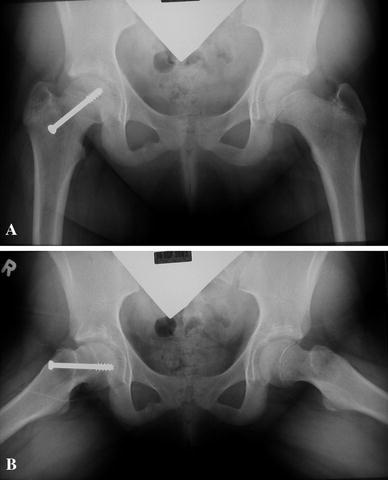

Fig. 2.

a Anteroposterior and b frog-lateral radiographs of a patient with a previous SCFE who was not diagnosed with AVN of the femoral head